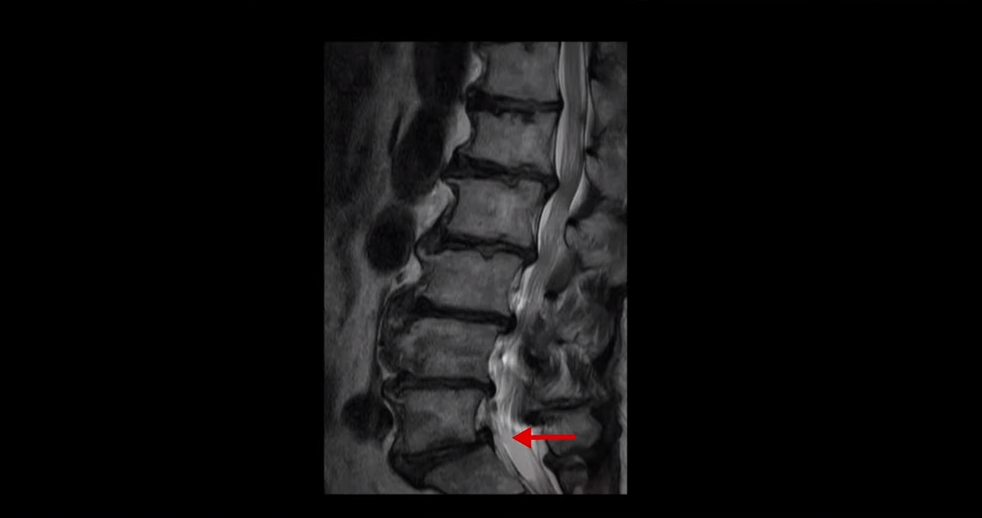

먼저 이분 MRI를 보면서 설명해 드린 후 이분 말씀 더 들어보겠습니다. MRI를 보시면 허리 5마디 전부가 퇴행이 심하고 안 좋습니다.

모든 마디에 중심성 협착

또는 추간공 협착이 있고

5번 1번에는 전방전위증이 있습니다.

그래서 대학병원에서도 다섯 마디 다 나사를 박아서 묶는 유합술을 하라고 권유한 겁니다.

이분의 이런 허리 퇴행 상태를 보면 아주 오랜 기간 허리가 아팠을 수밖에 없고 특히 오른쪽 신경가지가 빠져나가는 추간공이 많이 좁아져 있어서 오른쪽 다리가 심하게 저리고 아픕니다. 그런데 이렇게 여러 마디가 안 좋은 환자가 어떻게 수술 없이 치료가 가능할까요? 좁아진 신경 구멍을 수술로 넓혀야만 좋아지는 것 아닐까요? 전혀 그렇지 않습니다.